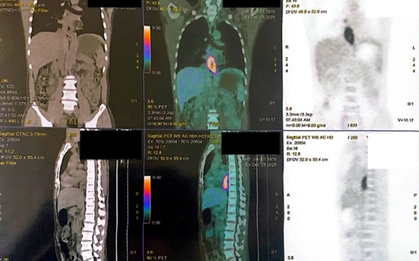

Chỉ có 2 dấu hiệu, người đàn ông phát hiện cùng lúc 2 bệnh ung thư

Sức khỏe

-

Một người bệnh 64 tuổi đồng thời mắc hai bệnh ung thư riêng biệt, một ở bàng quang, một ở ống mật chủ. Đáng nói, ông chỉ có 2 triệu chứng.